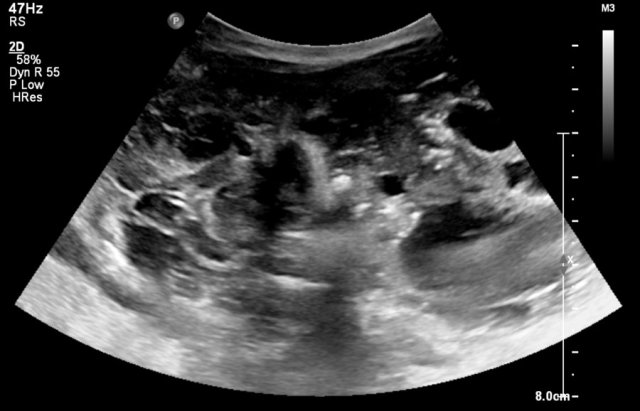

The image is of a one-month-old boy with a MCKD on prenatal ultrasound.

Some tissue and several large cysts are seen.

On Tc-99-DMSA scintigraphy no uptake was seen on the left side.

This is compatible with a MCKD.